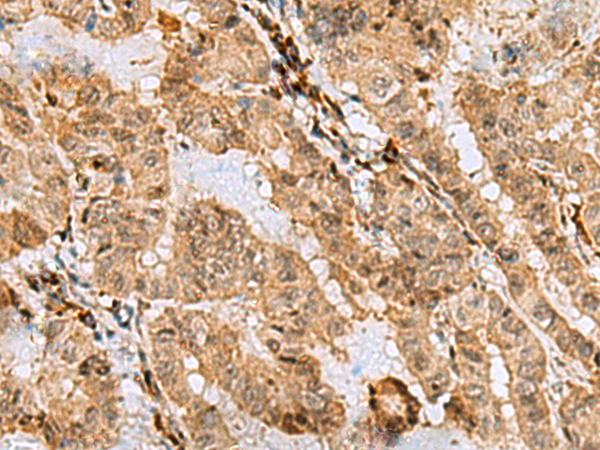

The image is immunohistochemistry of paraffin-embedded Human thyroid cancer tissue using (ASNA1 Antibody) at dilution 1/70.